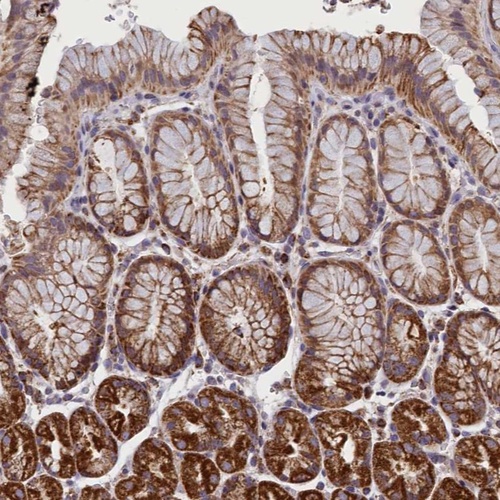

Immunohistochemical staining of human stomach shows strong cytoplasmic positivity in glandular cells.